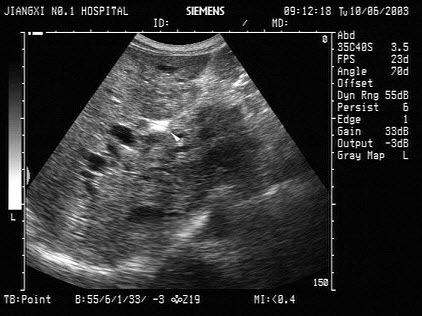

6、单项选择题

某患者左肾超声声像图如下,最可能的诊断为()

A.多发性肾囊肿

B.肾结核

C.多囊肾

D.重度肾积水

E.中度肾积水